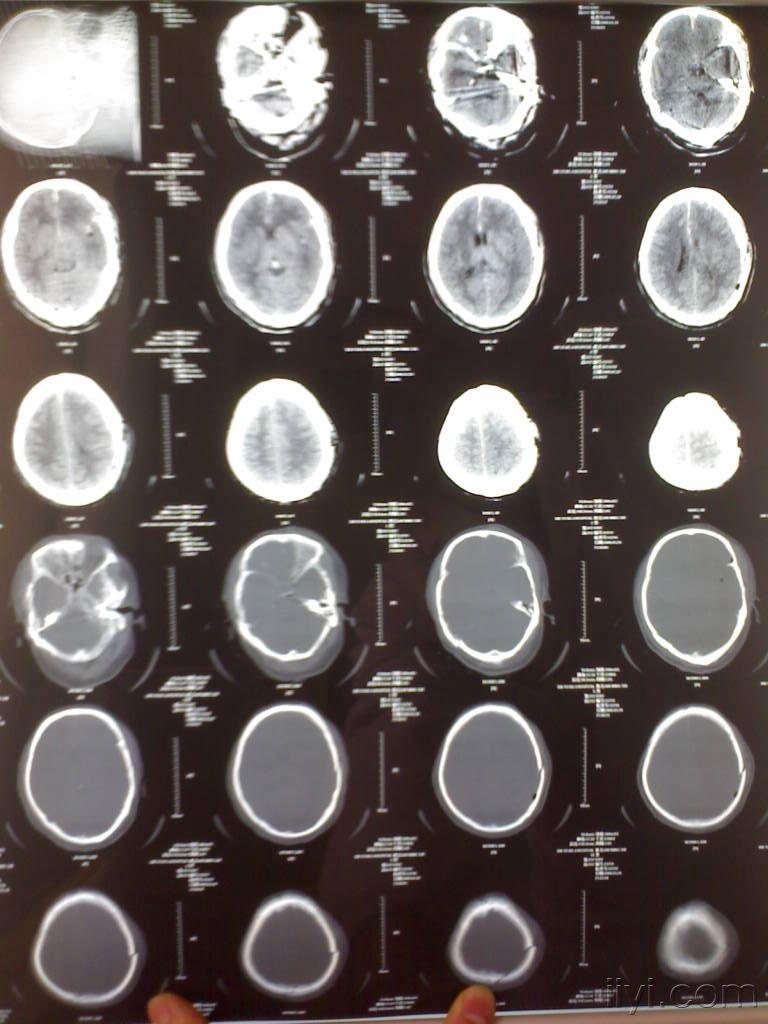

一例颅脑损伤的病例!请过脑外科博士读片指导解难(有最新进展了!).